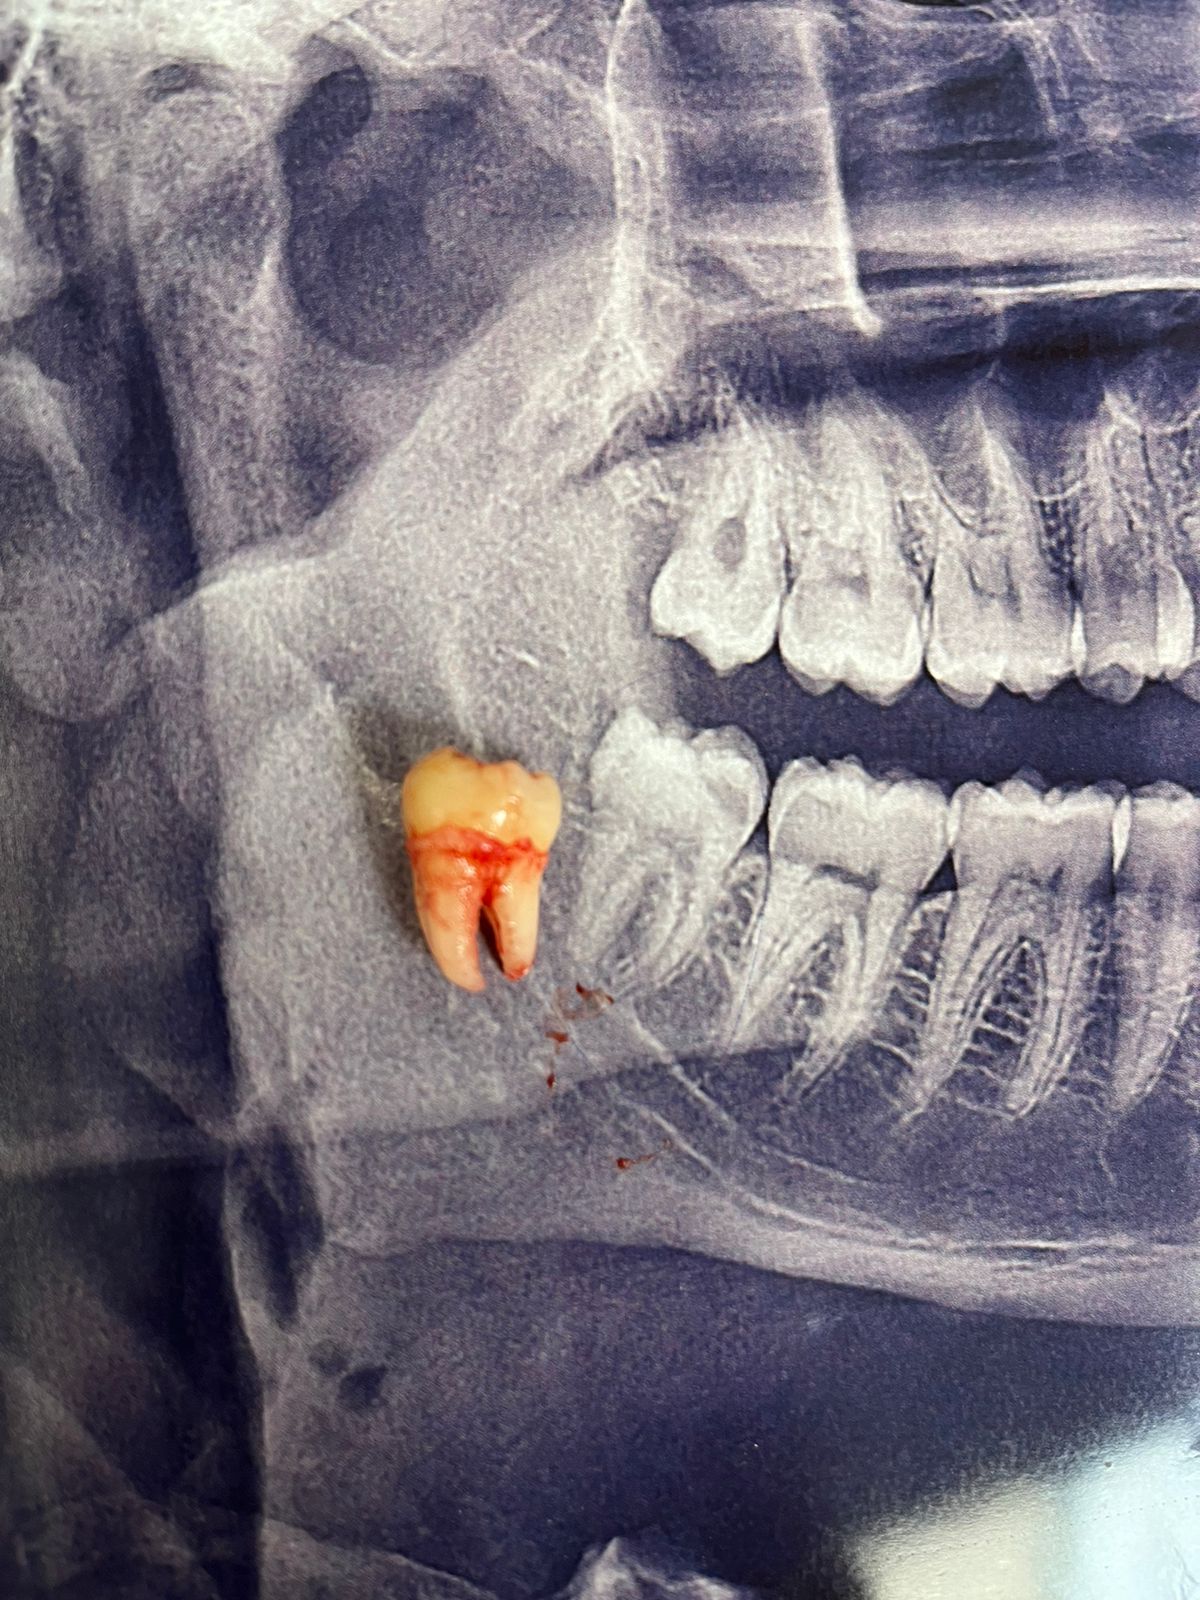

I started my internship at the maxillofacial surgery department at Al-Shifa Hospital, assisting in a few surgeries. However, the war began, bringing immense suffering and a series of tragic events and circumstances. To salvage what was left of my future and dreams, I decided to go to Egypt. My family remains in Gaza, enduring random bombings, killings, hunger, and displacement. While I managed to survive, I feel like I didn’t truly survive. I constantly worry about my family and the dire conditions they are facing. I hope God will protect them and bring an end to this genocide and brutal war.